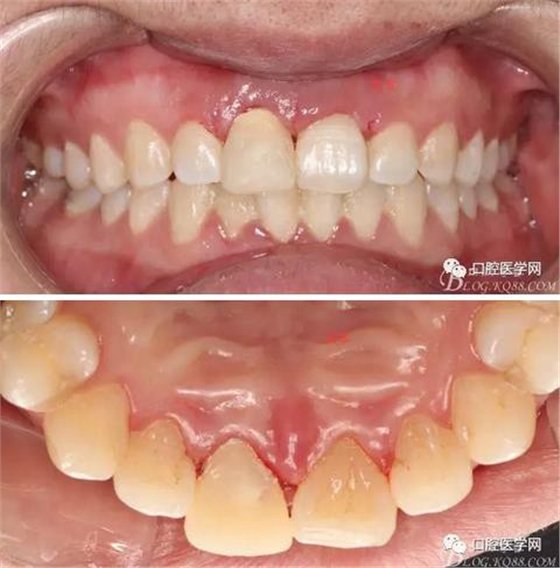

牙冠延長術(shù)后6周復(fù)診牙齦齦緣形態(tài)恢復(fù)良好,齦乳頭有些欠缺,患者著急永久修復(fù)。

備牙

戴牙